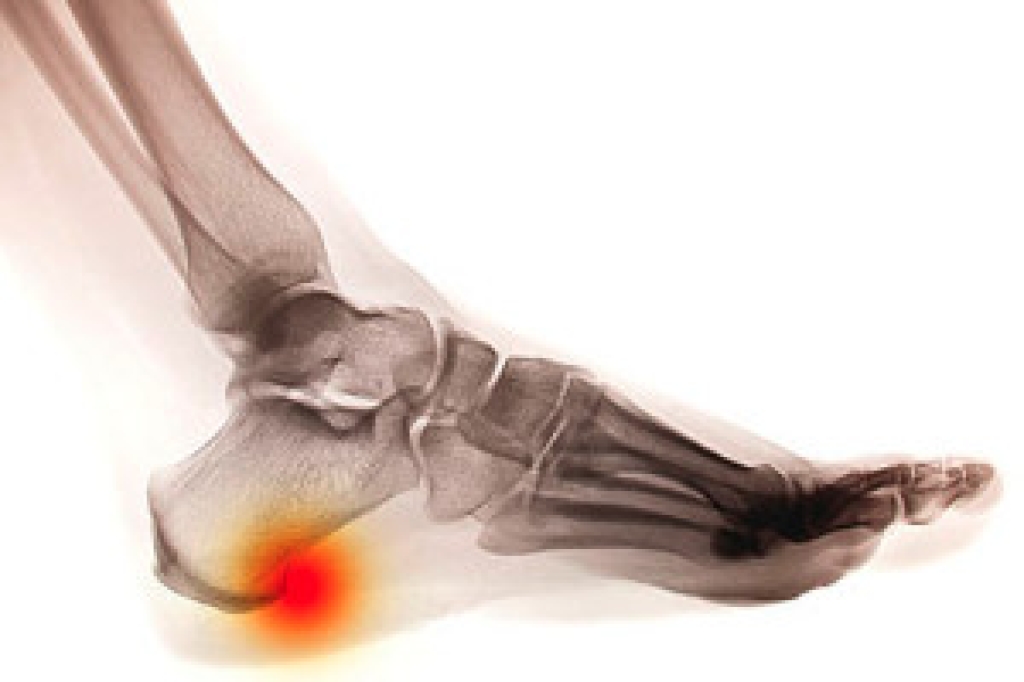

Heel pain is often associated with plantar fasciitis. The plantar fascia is a band of tissues that extends along the bottom of the foot. A rip or tear in this ligament can cause inflammation of the tissue.

Heel spurs are another cause of pain. When the tissues of the plantar fascia undergo a great deal of stress, it can lead to ligament separation from the heel bone, causing heel spurs.